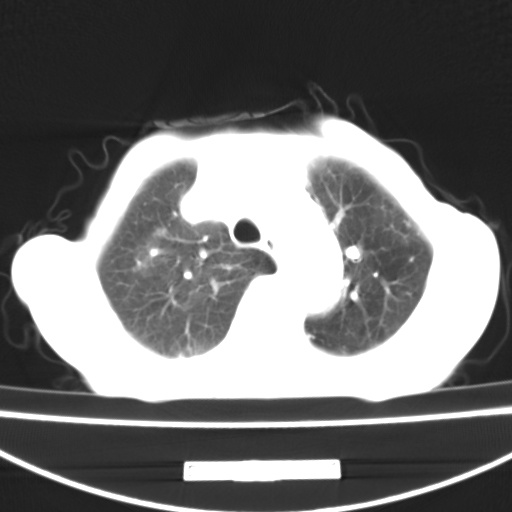

患者 女 67岁,反复咳嗽咳痰2年,加重伴喘及双下肢浮肿1月

陈旧性肺结核、慢性支气管炎、支气管扩张症、肺心症、肺动脉高压。

诸大血管及f肺门血管增粗迂曲.左下肺多发薄壁空腔影.部分非也透亮度增高.薄曾扫描可区分肺气肿类型.考虑1.慢性支气管炎 2.左下肺支气管扩张 3.肺气肿 4 肺动脉高压5.是否有先心病病史

考虑1.慢性支气管炎 2.左下肺支气管扩张 3.肺气肿 4 肺动脉高压

慢支炎、肺气肿、双肺感染、左下囊状支扩。

慢支、肺气肿、肺动脉高压;左下肺囊状支扩并粘液栓形成。